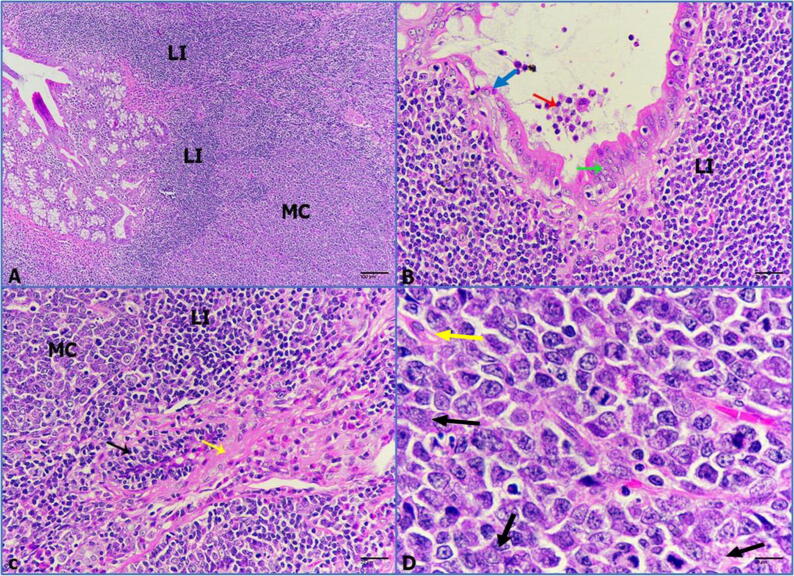

Histological sections of colorectal tissue were stained with Hematoxylin and Eosin (H&E). Tumor formation was detected in the colon tissue of treated rats. As shown in Fig. 6A microscopic analysis showed that rats treated with DMH exhibited heavy development of colorectal tumors. The tumors were classified according to the changes in the colon region such as; medullary carcinoma, which is surrounded by a huge presence of lymphocytic infiltration (LI). Additionally, intestinal glands showed mucosal hyperplasia and dysplasia, which is filled with necrotic debris (Fig. 6B). Moreover, medullary carcinoma originated in the submucosa layer as sheet-like cellular growth infiltrated with lymph nodal depositions and desmoplastic reaction represented by proliferation of spindle cells (Fig. 6C). Furthermore, tumor cells displayed amphiphilic cytoplasm, pleomorphic nuclei, and dispersed chromatin (Fig. 6D). As shown in Fig. 7 A-B, the intestine of untreated rats revealed a normal histological feature of the mucosal, submucosal, and muscularis layers with no abnormal lesions or changes. Also, intestinal glands were abundant in the mucosa-associated with numerous goblet cells and solitary lymphoid nodes. On the other hand, it is noteworthy that the histological examination of intestinal tissue of IVM-treated groups (0.25, 0.5, 1 mg/kg) illustrated no abnormalities or signs of pathological alterations (Fig. 7 C-D). After induction of colorectal tumor, treated rats with a low dose of IVM displayed no significant effects on the histological level. Medullary carcinoma looked large and infiltrated with lymphoid nodules and desmoplastic reaction (Fig. 8 A-B). Medium dose revealed a reduction in the medullary carcinoma that encroached the lymphoid nodules and desmoplastic reaction with great incidence (Fig. 9 A-B). Finally, a high dose showed a marked reduction in medullary carcinoma incidence manifested by dispersed carcinoma cells besieged with the lymphocytic infiltration (Fig. 10 A-B).

Fig. 6.

(A-D): Photomicrographs of medullary carcinoma of colon, medullary carcinoma (MC), lymphoid infiltration (LI), hyperplasia (green arrow), dysplasia (blue arrow), necrotic debris (red arrow), desmoplastic reaction (yellow arrow), spindle cells (black arrow). A: heavy incidence of medullary carcinoma infiltrated by lymphoid nodules (H&E-100×). B: epithelial hyperplasia of intestinal glands filled with necrotic debris in its lumen (H&E-400×). C: medullary carcinoma surrounded by lymphoid infiltration and desmoplastic reaction with spindle cells (H&E-400×). D: carcinoma cells with amphophilic cytoplasm (pink arrows) and pleomorphic nuclei (H&E-1000×).